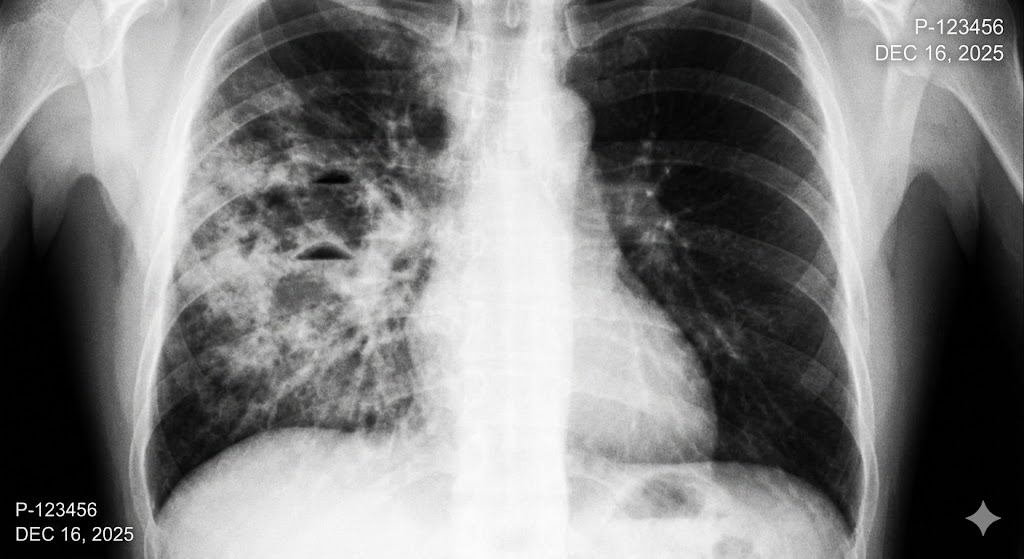

比較:特発性間質性肺炎(特に特発性肺線維症:IPF)の予後

肺炎の中で特殊なタイプになりますが、慢性的に進行する原因不明の肺炎の代表です。

治療法が少なく、肺炎の中で予後が最も悪いタイプの1つです。

急性増悪したときの致死率は誤嚥性肺炎よりも高くなりますが、長期生存期間では誤嚥性肺炎よりも長くなっています。

- 急性増悪の恐怖: 急性増悪が起こることもあり、非常に致死的な状況になりやすいものです。一度起こすと、その後1〜2ヶ月で亡くなるケースも少なくありません。